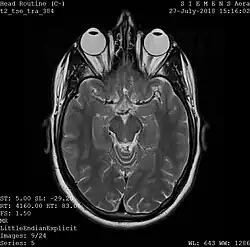

One frame of an MRI scan of the head showing the eyes and brain

A magnetic resonance imaging instrument (MRI scanner), or "nuclear magnetic resonance (NMR) imaging" scanner as it was originally known, uses powerful magnets to polarize and excite hydrogen nuclei (i.e., single protons) of water molecules in human tissue, producing a detectable signal which is spatially encoded, resulting in images of the body.[12] The MRI machine emits a radio frequency (RF) pulse at the resonant frequency of the hydrogen atoms on water molecules. Radio frequency antennas ("RF coils") send the pulse to the area of the body to be examined. The RF pulse is absorbed by protons, causing their direction with respect to the primary magnetic field to change. When the RF pulse is turned off, the protons "relax" back to alignment with the primary magnet and emit radio-waves in the process. This radio-frequency emission from the hydrogen-atoms on water is what is detected and reconstructed into an image. The resonant frequency of a spinning magnetic dipole (of which protons are one example) is called the Larmor frequency and is determined by the strength of the main magnetic field and the chemical environment of the nuclei of interest. MRI uses three electromagnetic fields: a very strong (typically 1.5 to 3 teslas) static magnetic field to polarize the hydrogen nuclei, called the primary field; gradient fields that can be modified to vary in space and time (on the order of 1 kHz) for spatial encoding, often simply called gradients; and a spatially homogeneous radio-frequency (RF) field for manipulation of the hydrogen nuclei to produce measurable signals, collected through an RF antenna.

Like CT, MRI traditionally creates a two-dimensional image of a thin "slice" of the body and is therefore considered a tomographic imaging technique. Modern MRI instruments are capable of producing images in the form of 3D blocks, which may be considered a generalization of the single-slice, tomographic, concept. Unlike CT, MRI does not involve the use of ionizing radiation and is therefore not associated with the same health hazards. For example, because MRI has only been in use since the early 1980s, there are no known long-term effects of exposure to strong static fields (this is the subject of some debate; see 'Safety' in MRI) and therefore there is no limit to the number of scans to which an individual can be subjected, in contrast with X-ray and CT. However, there are well-identified health risks associated with tissue heating from exposure to the RF field and the presence of implanted devices in the body, such as pacemakers. These risks are strictly controlled as part of the design of the instrument and the scanning protocols used.

Because CT and MRI are sensitive to different tissue properties, the appearances of the images obtained with the two techniques differ markedly. In CT, X-rays must be blocked by some form of dense tissue to create an image, so the image quality when looking at soft tissues will be poor. In MRI, while any nucleus with a net nuclear spin can be used, the proton of the hydrogen atom remains the most widely used, especially in the clinical setting, because it is so ubiquitous and returns a large signal. This nucleus, present in water molecules, allows the excellent soft-tissue contrast achievable with MRI.[13]